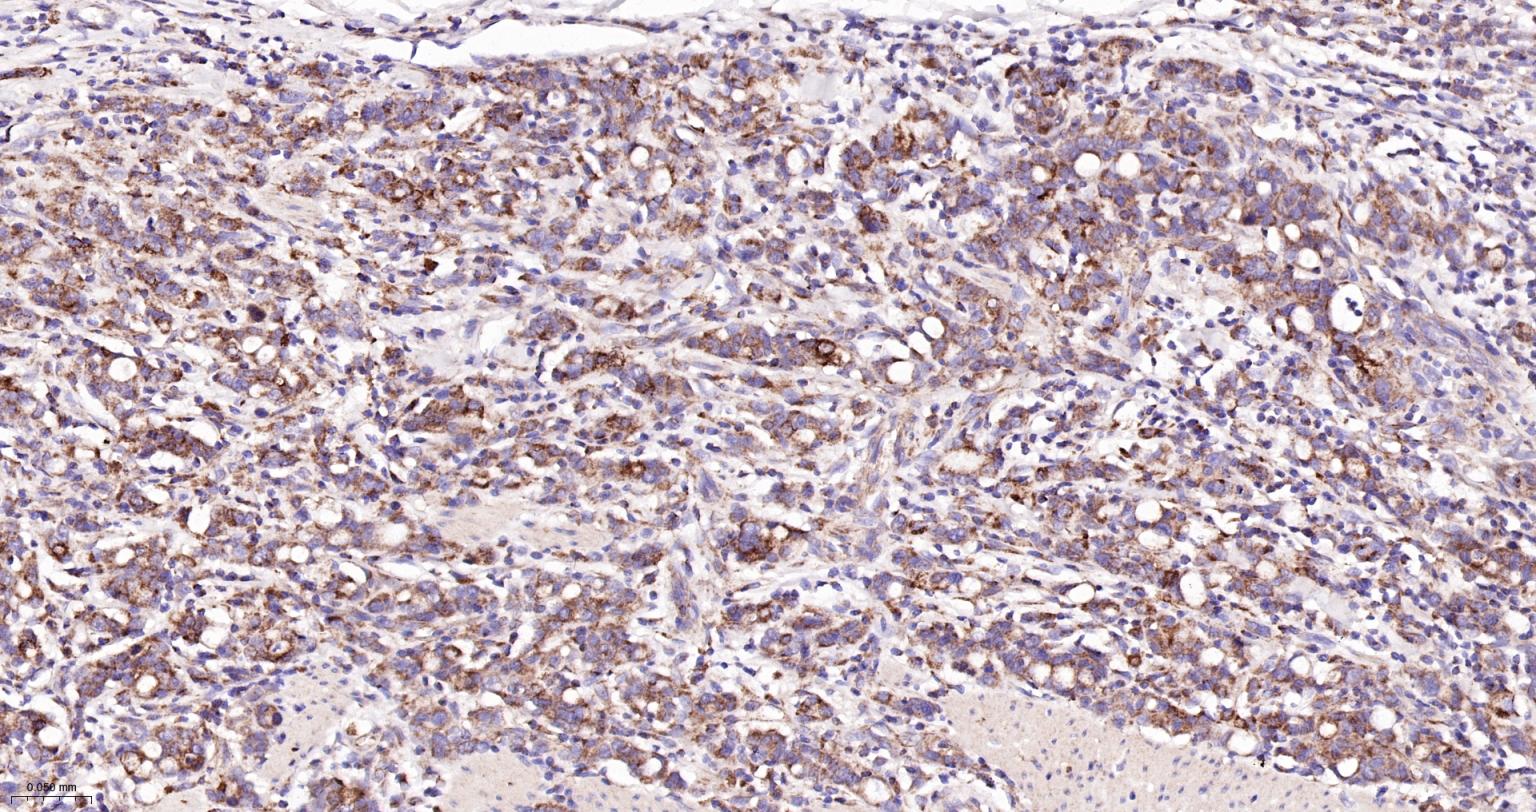

Paraformaldehyde-fixed, paraffin embedded Human Gastric Cancer; Antigen retrieval by boiling in sodium citrate buffer (pH6.0) for 15 min; Antibody incubation with Bak Monoclonal Antibody, Unconjugated(bsm-61174R) at 1:200 overnight at 4°C, followed by conjugation to the SP Kit (Rabbit, SP-0023) and DAB (C-0010) staining.